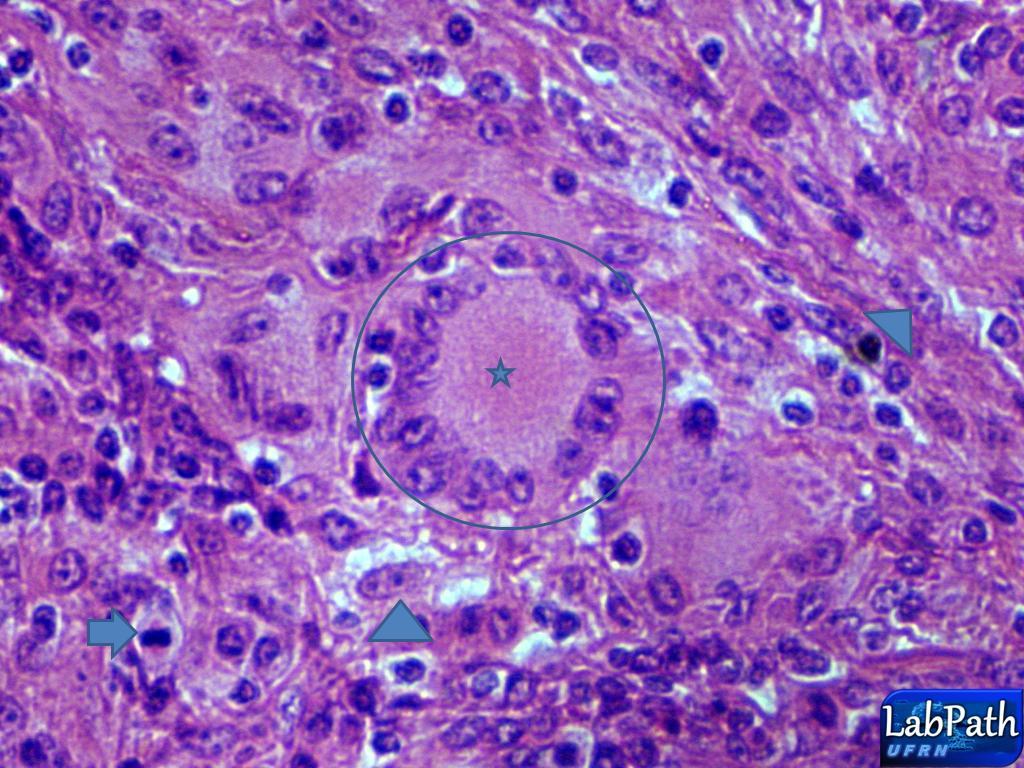

Granuloma caseoso: pensar em…

TUBERCULOSE!

Imunidade CELULAR